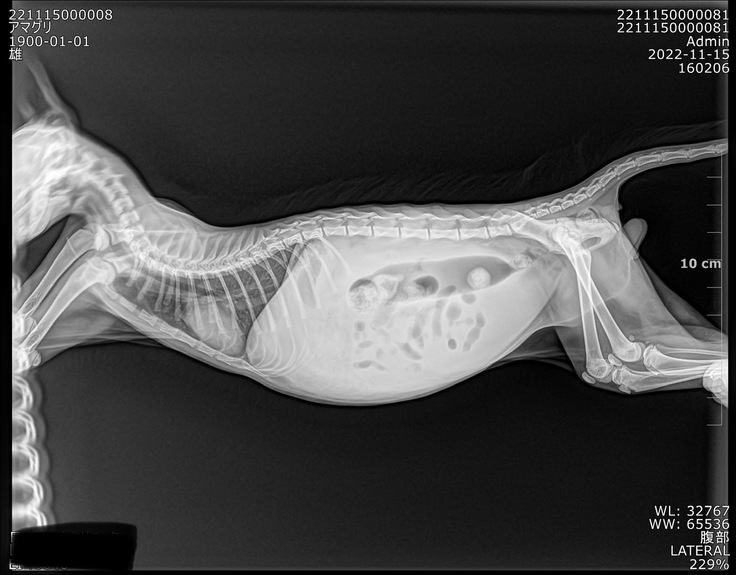

お腹が膨れ上がりおかしいと思い、近くの病院に行った所、膀胱炎の初期と診断され抗生物質と消炎剤の薬を10日分出され1日1回あげていましたが、一向によくならない為別の病院に行き血液検査をしてもらったところFIPの可能性があると診断されました。

猫伝染性腹膜炎(FIP)は、多くは1歳未満の子猫で発症します。発熱、沈うつ、食欲不振、体重減少、黄疸、腹水でおなかがふくれるなどの症状が起こり、進行が速いと診断後1ヶ月以内で亡くなることも少なくありません。

ウェットタイプは、胸膜や腹膜などの内臓を覆う膜に炎症が起きる「胸膜炎」や「腹膜炎」と、血管炎を特徴とします。これにより、腹水、胸水、心嚢水、陰嚢水が貯留します。胸水の貯留により、呼吸がしにくく苦しくなることがあります。ウェットタイプは進行が速く、診断後2週間〜1ヶ月程度で亡くなることもあります。

腹水がたまりご飯もほとんど食べなくなりじっとしているあまぐり。日に日に痩せていっているようで

無事病院に到着し検査と治療の為そのまま入院、手遅れになるといけないのでFIP治療、投薬を開始しました。